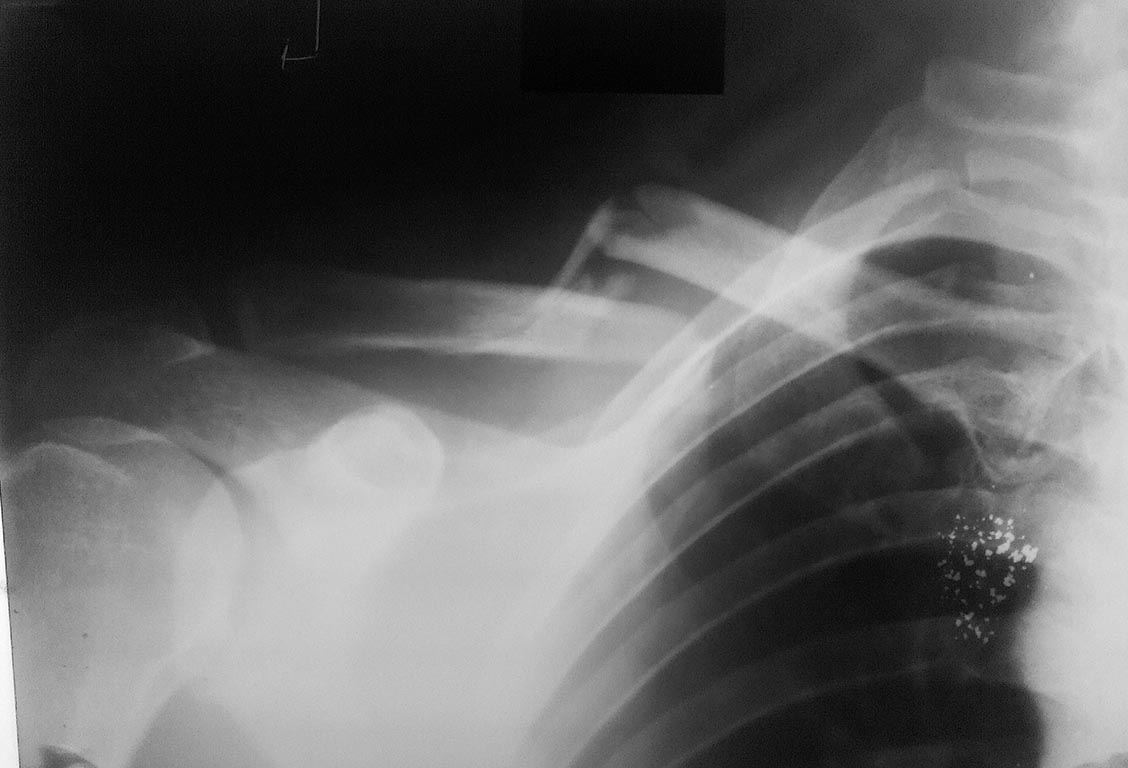

Мужчина, 35 лет, 23.11.15 получил закрытый оскольчатый перелом левой

ключицы в результате падения на руку с высоты роста. 26.11.15 выполнена

операция: Открытая репозиция, интрамедуллярный остеосинтез штифтом

Богданова, промежуточные осколки фиксированы на место лавсановыми

нитями. Остеосинтез выполнил по классической методике: через доступ

длинной 5 см экономно скелетировал отломки, рассверлил сверлом 3.2 мм

каналы в дистальном и проксимальном отломках, подобрал соответствующего

диаметра стержень Богданова, который антеградно ввбил в репонированные

отломки,промежуточные осколки фиксировал лигатурами к месту перелома.

Смущает одно, что изначально стержень не изгибал под S-образную кривизну

ключицы, а на R-графии после остеосинтеза стержень деформировался под

изгиб ключицы.

Изначально планировал стержень расположить "широкой" частью фронтально,

но не вышло.